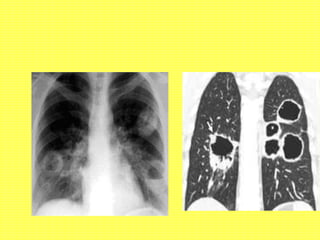

• Chest X ray / HRCT thorax:

-Pulmonary infiltrates- small vessel vasculitis

-Pulmonary cavities- Wegener’s granulomatosis

Wegener’s Granulomatosis

• Classical triad  URT + LRT + renal

• Chronis sinusitis, Pulmonary nodules,

Pulmonary cavities, Rapidly Progressive

Glomerulonephritis